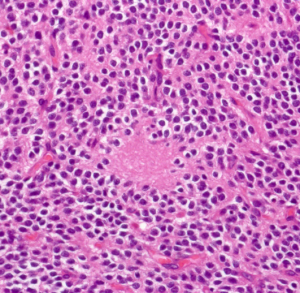

病理所見

免疫染色(Olig2)。HE染色で核周囲が明るく抜ける形態からoligodendrogliomaが鑑別となるが、Olig2は陰性で、oligodendrogliomaは否定される。

免疫染色(Synaotphysin:神経内分泌marker)。腫瘍細胞間の細線維性基質に陽性を示す。